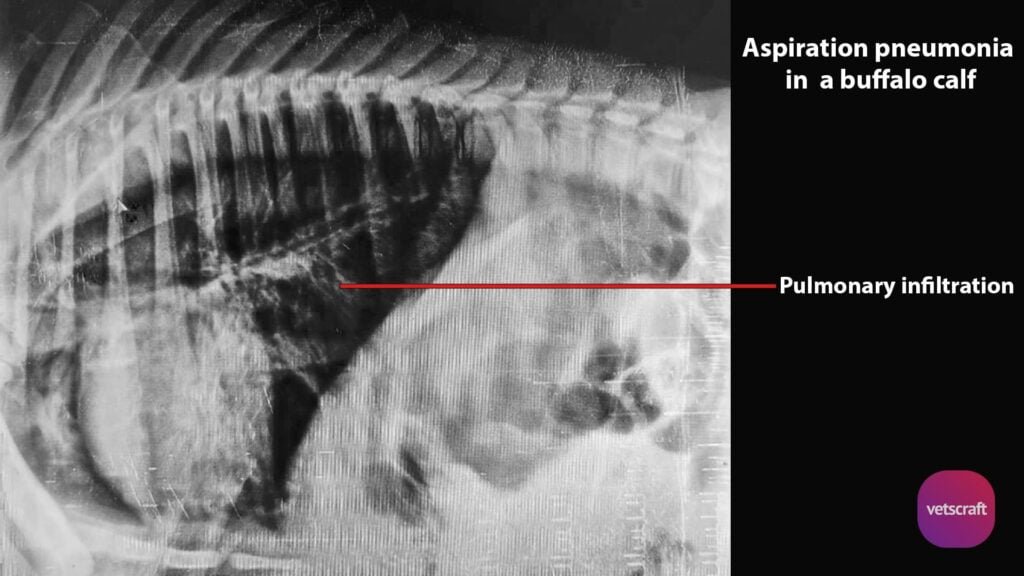

Veterinary Surgery and RadiologyStructures or organs can be evaluated more effectively for their size, shape and position by use of contrast radiography in animals.